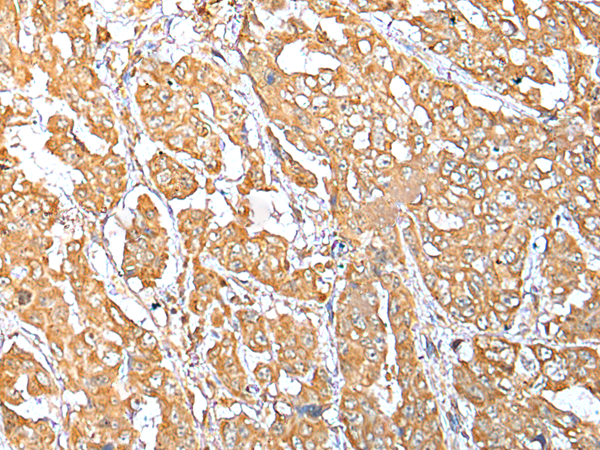

IHC positive control: |

Human breast cancer and human esophagus cancer |

IHC Recommend dilution: |

25-100 |